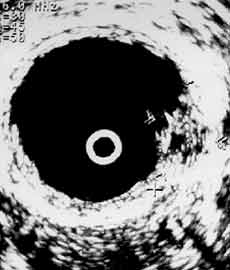

Рис. 5 и 6. Цистэндосонограммы. (Слева) Рак мочевого пузыря стадия Т2в. (Справа) Рак мочевого пузыря стадия Т3а. Мышечная стенка полностью разрушена.